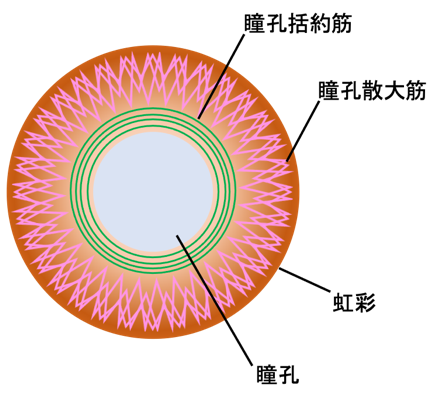

さて話を進める前に瞳孔支配についておさらいです。

瞳孔の大きさは、自律神経系によって調節されています。

・ 副交感神経:動眼神経経由で瞳孔括約筋を収縮 → 縮瞳

・ 交感神経:瞳孔散大筋を収縮 → 散瞳

散瞳を伴う瞳孔不同は、眼疾患、神経疾患、薬剤投与によって起こり、神経疾患では動眼神経麻痺や脳幹の病変を疑うことが多いです。

*紹介論文より改変